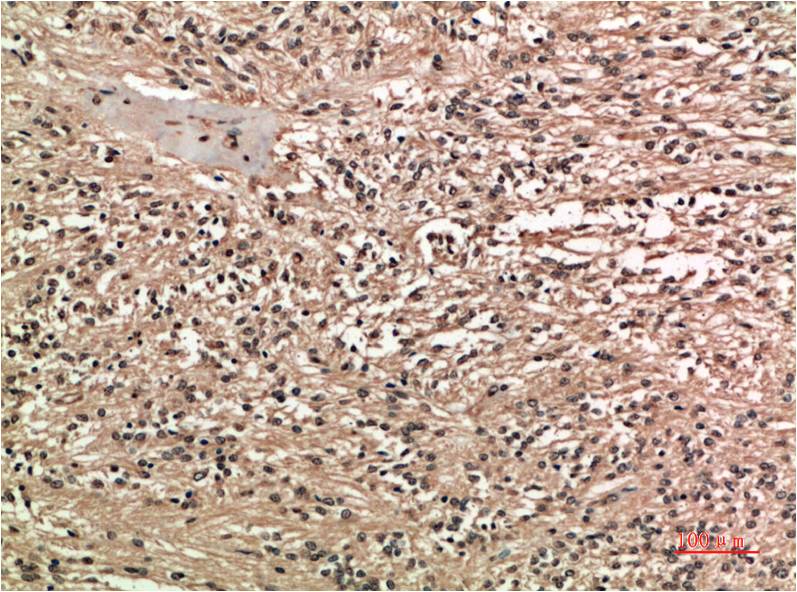

COX-2 Mouse Monoclonal Antibody(2G1)

Catalog NO.:BE3661

Applications :IHC

Reactivity :H,R,M

Recommended dilutions: IHC 1:100-200

Specificity: The COX-2 Mouse Monoclonal Antibody can detects endogenous COX-2 proteins.